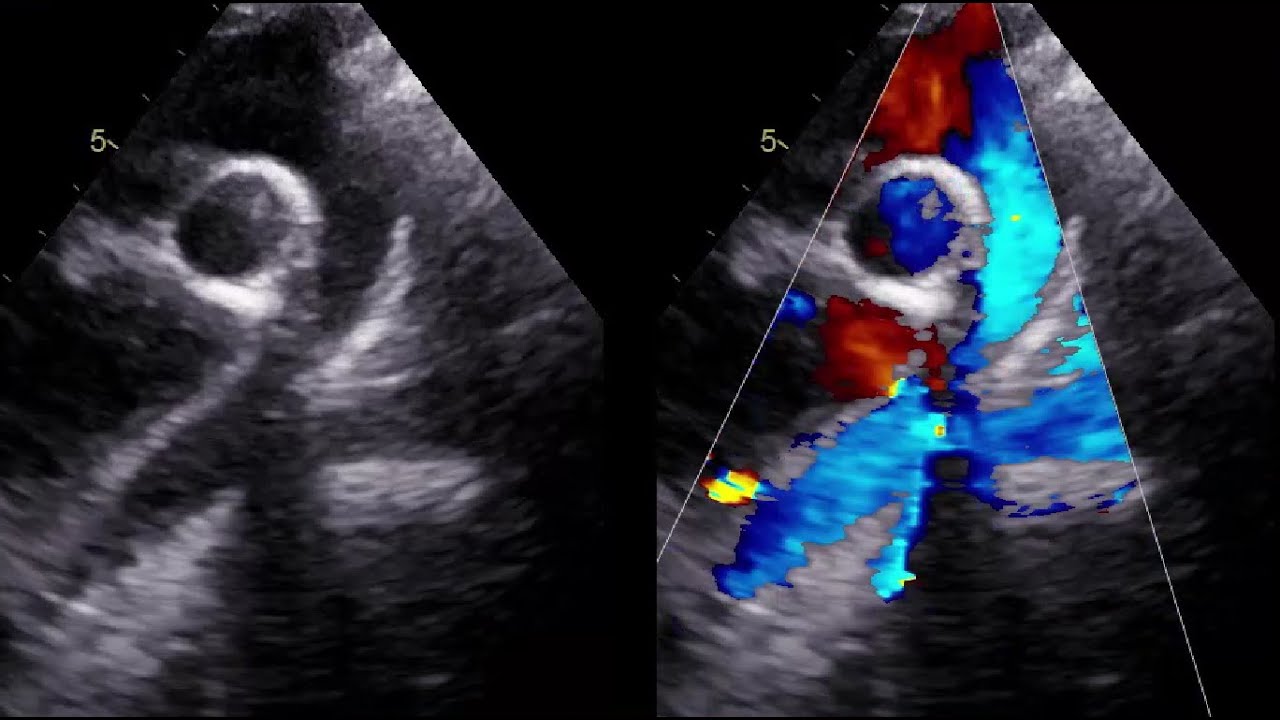

I am starting short series about common mistakes in pediatric echocardiography imaging.

This video discusses the point of ideal vs non ideal aortic arch in supra sternal window.